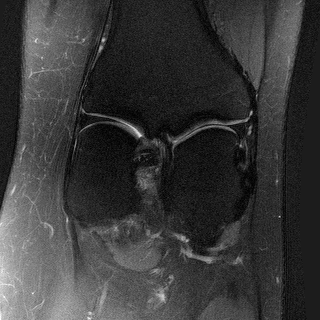

MRI with multi-contrast side information: We use fastMRI knee dataset (Zbontar et al., 2018) with the ContextMRI model (Chung et al., 2025). We pair PD and PDFS contrasts, reconstructing one from the other under undersampling with 2% ACS. We use normalized mutual information (NMI) as reward, which is robust to contrast changes. Fig. 6 highlights sharper edges and more faithful structure. Table 10 in Appendix D.3 shows our methods consistently improves the baseline in all the metrics of interest.

Side

Measurement

ContextMRI

RFJSearch (Ours)

Ground Truth

PDFS with PD

PD with PDFS

We used the contrast-pairings among the files in the fastMRI dataset, provided by (Atalık et al., 2025). We collect the data from the (fastMRI) source and preprocess to be compatible with the inputs in ContextMRI. Specifically, the setup used in the data is multi-coil MRI acquisition, which requires us to estimate the coil sensitivity maps, and then a complex reconstruction from them. ContextMRI takes complex values as inputs and denoises to produce a complex-valued 2D image. We computed NMI with bins at each step of the diffusion process to balance complexity with performance. We use the defaults parameters as in ContextMRI, except for the acceleration factor, and the center fraction (ACS), . We use a pair of anatomy which two contrasts, which has more 30 slices. We consider the slices to as these are more challenging and report the results by using one as the side information for the other.

| PDFS with PD | ||||

|---|---|---|---|---|

| Algorithm | PSNR () | SSIM () | LPIPS () | NMI () |

| RFJS | 25.85 | 0.801 | 0.375 | 0.457 |

| GS | 25.33 | 0.797 | 0.375 | 0.455 |

| BON | 25.47 | 0.797 | 0.376 | 0.454 |

| ContextMRI | 25.39 | 0.795 | 0.383 | 0.451 |

| PD with PDFS | ||||

| RFJS | 27.85 | 0.920 | 0.358 | 0.579 |

| GS | 27.80 | 0.920 | 0.360 | 0.579 |

| BON | 27.80 | 0.918 | 0.366 | 0.570 |

| ContextMRI | 27.46 | 0.915 | 0.375 | 0.563 |